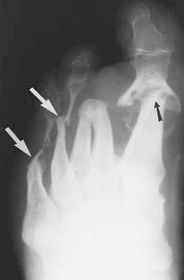

What disease is this? What do the arrows indicate? | Gout Arrows = 'punched out' erosions |

What disease is this? What indicates this? | Tophaceous gout. Soft tissue swelling surrounding the index finger PIPJ, with associated erosion and bone resorption |